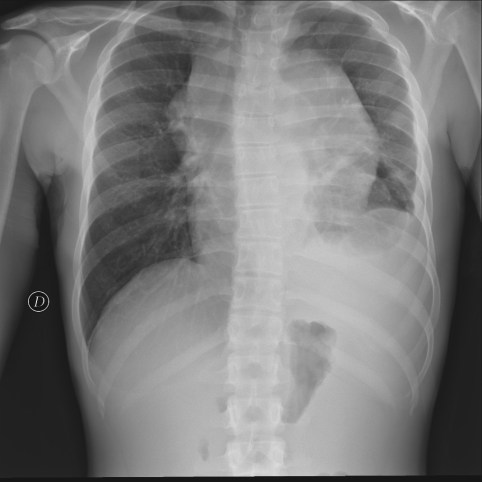

CASO: sospecha de neumonía.

Hallazgos:

- En un principio podríamos decir que existe un aumento de densidad retrocardiaco que podría ser compatible con condensación neumónica a dicho nivel, sin embargo estamos ante una placa poco inspirada, lo cual puede llevarnos a cometer errores diagnósticos.

- Se recomendó volver a realizar la radiografía, observar a continuación:

Ya no se observa el aumento de densidad retrocardiaco, la placa es normal.

INSPIRACIÓN: Una placa bien inspirada es aquella en la que se observar 6-7 arcos costales anteriores o 10-11 arcos costales posteriores. Lo contrario puede producir imágenes falsas de condensaciones o de seudocardiomegalia.